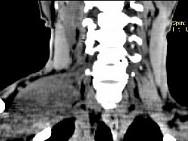

问题 女,47岁,下颈部触及一包块约五年余,CT如图所示,最可能诊断为 ( )

选项 A、副神经节瘤 B、巨淋巴结增生症 C、血管瘤 D、神经鞘瘤 E、滑膜肉瘤

答案 D